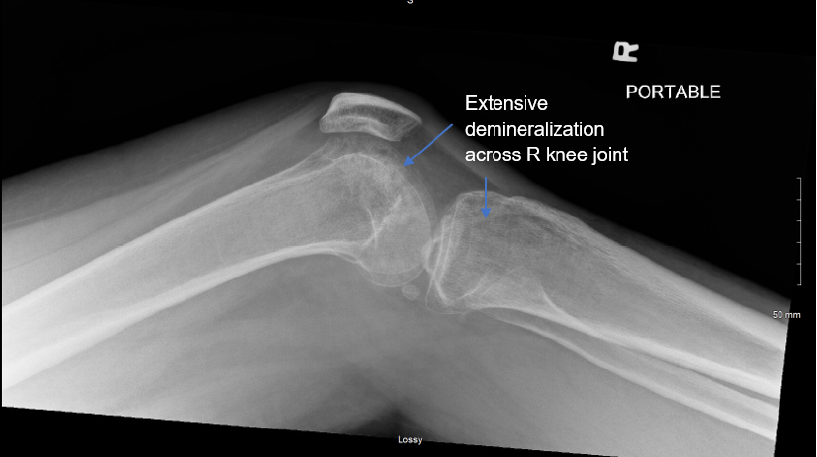

Case Report: Transient Osteoporosis of Pregnancy in the Knee

Nhi Tran and Woojin Chong. 6(2): 52-56.